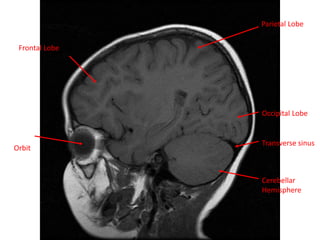

Frontal Lobe

Temporal

Lobe

Parietal Lobe

Occipital

Cerebellum

Orbit

Occipital Lobe

Transverse sinus

Cerebellar

Hemisphere

Frontal Lobe Parietal Lobe Orbit OccipitalLobe Transverse sinus Cerebellar Hemisphere